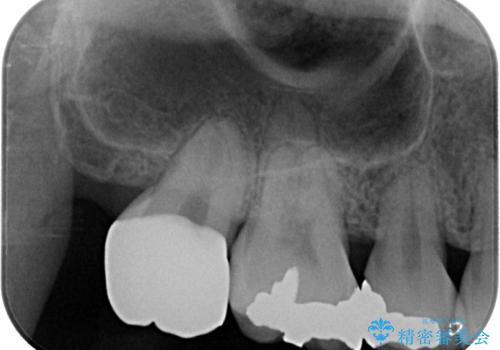

セラミッククラウンの適合はレントゲン写真からも分かる通り、境界がぴったりと合った、高適合のものとなりました。

矯正治療により処置が可能な位置に歯が移動したため、オールセラミッククラウンにて補綴治療を行うこととしました。